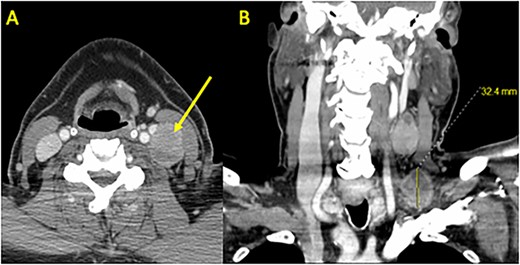

A 68-year-old male with prior history of non-Hodgkin’s lymphoma presented with 3-week history of progressively painful 3 cm supraclavicular neck mass. Computed tomography (CT) scan revealed a 1.3 cm left thyroid lobe nodule and 3 cm left level 3 and 4 lymphadenopathy (Fig. 1). Ultrasound-guided fine needle aspiration was positive for PTC. Two months later, the patient underwent a total thyroidectomy and central & left neck lymph node dissection (Fig. 2). Pathology showed a classical variant PTC, measuring 1.6 cm in the left lobe of the thyroid, with prominent fibrosis and lymphovascular invasion. Neck dissection of levels 2–4 and 6 yielded 16/42 positive nodes with presence of extranodal extension. Molecular testing revealed BRAF V600E positivity and staged as T1N1bMx.

Preoperative CT Scan with Contrast. (A) Axial and (B) coronal sections demonstrating bulky left neck lymphadenopathy. Shown are a 3.2 × 2.8 cm level 4 mass in the supraclavicular fossa and a 3.9 × 2.3 cm level 3 mass adjacent to the internal jugular vein and carotid artery. A left thyroid 1.3 cm nodule was identified (not shown) and confirmed as PTC using fine needle aspiration.